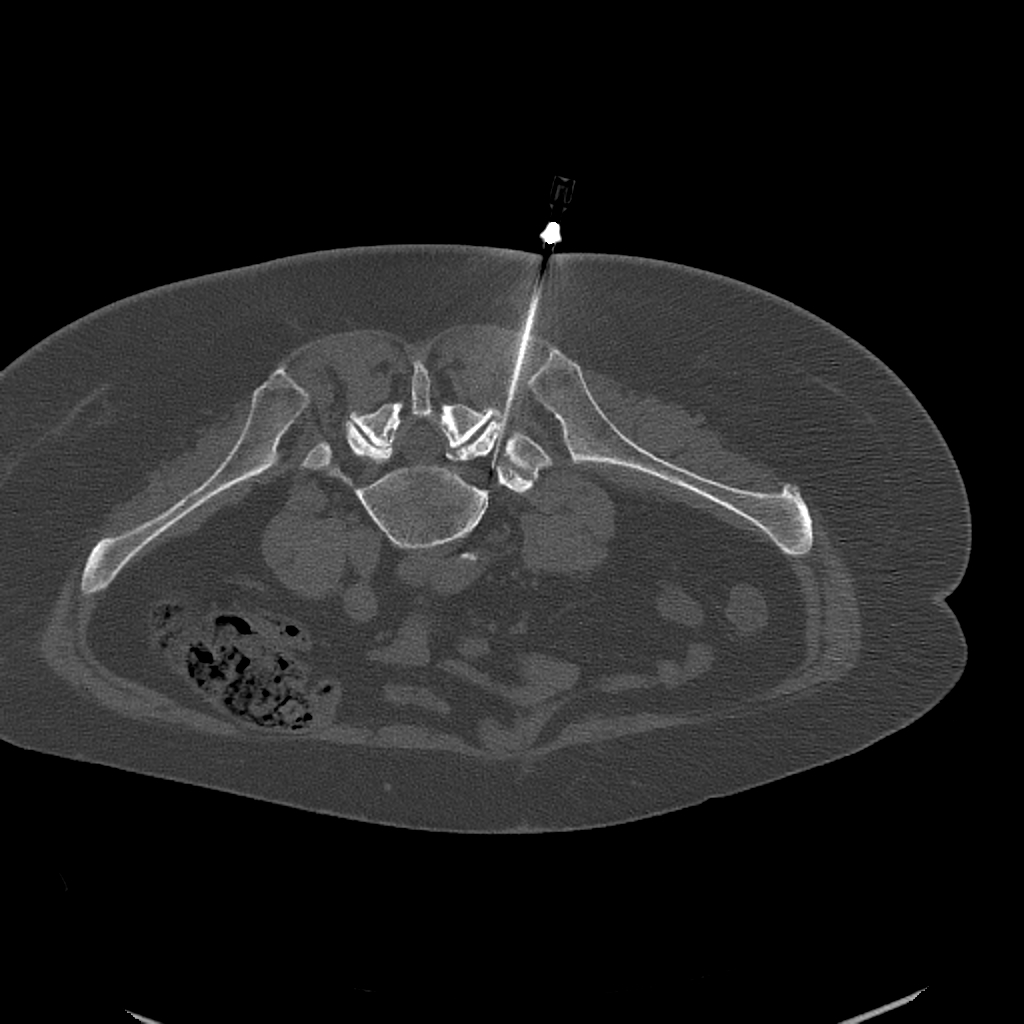

CT-vezérelt ideggyöki blokád — axiális CT-felvétel a tű pozíciójával

CT-vezérelt ideggyöki blokád: a felvételen jól látható a tű pontos pozícionálása az érintett ideggyök mellé

Ha a csigolyák közötti részen kilépő idegpár a fájdalom forrása — például porckorongsérv vagy gerinccsatorna-szűkület miatti becsípődés esetén — célzott ideggyöki blokád injekciós terápiára van szükség. A beavatkozás során minimális mennyiségű helyi érzéstelenítőt és gyulladáscsökkentő szteroidot juttatunk az érintett ideggyök mellé.

A tű pontos célzását CT-vel vagy röntgen képerősítővel ellenőrizzük, hogy kizárólag a gyulladt idegeket érintse a kezelés. Az érzéstelenítő hatására átmeneti zsibbadás vagy gyengülés jelentkezhet — ez természetes jelenség, jellemzően néhány órán belül elmúlik.